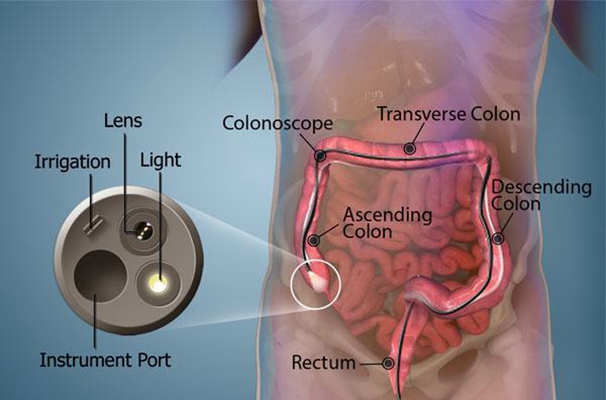

盲腸的位置 (50)

盲腸的位置 (6)

盲腸的位置 (7)

盲腸的位置 (8)

盲腸的位置 (9)

盲腸的位置 (46)

盲腸的位置 (47)

盲腸的位置 (48)

盲腸的位置 (49)

盲腸的位置 (5)

盲腸的位置 (42)

盲腸的位置 (43)

盲腸的位置 (44)

盲腸的位置 (45)

盲腸的位置 (41)

盲腸的位置 (40)

盲腸的位置 (30)

盲腸的位置 (31)

盲腸的位置 (32)

盲腸的位置 (33)